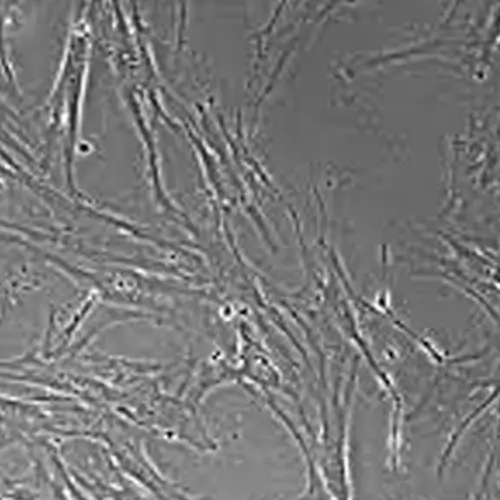

Cell Morphology:

Elongated and sometimes triangular in shape

Mesenchymal stem cells are multipotent adult stem cells, isolated from the stroma of adipose tissue and are of mesenchyme origin. They are multipotent in nature due to their ability to differentiate into cells of multiple origins including bone, cartilage, connective tissue, neurons, etc. They have fibroblast-like morphology and are adherent to culture vessels.